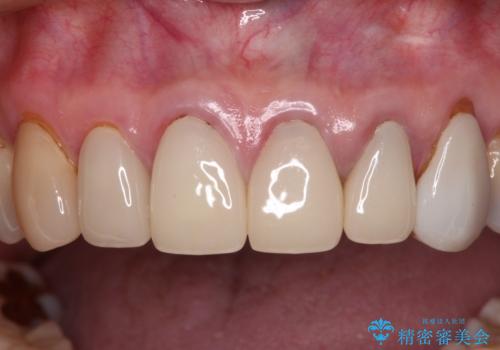

もげてしまった前歯をセラミッククラウンで自然に

- 前歯が土台ごと外れてしまったとのことで来院された患者様です。

土台は外れていましたが破折などの問題はなく、土台からの再治療で対応可能な状態でした。

隣の犬歯も神経が取り除かれていたしたが、ラミネートベニアで治療されており、裏側でむし歯が進行する可能性があったため、こちらも治療が必要と判断されました。

外れてしまったクラウンを保管しておき、新しいクラウン製作の際に技工所に送ることで、今までと同じような色合いに仕上げることができ、周囲のクラウンとバランスを取ることができます。